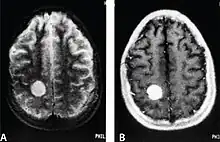

| MRI of a cardiac angiosarcoma that has metastasised to the brain. | |

Primary cardiac angiosarcoma is an angiosarcoma that arises in the heart. Despite being very rare they are the most common malignant primary heart tumor with 10–25%[12][3] of cases being angiosarcomas. Symptoms may include shortness of breath, chest pain (46%[12]), hypotension and syncope. Superior vena cava syndrome is reportedly a complication of cardiac angiosarcoma.[7] Due to the non-specificity of symptoms and rarity of the disease it is often missed by doctors and initial diagnosis may be delayed. A 2012 study reported that 56% of patients presented with pericardial effusion with or without cardiac tamponade.[12] The most common finding on imaging is cardiomegaly. Prognosis is generally very poor with a mean survival rate of three months to four years following diagnosis.[7] Metastasis at time of diagnosis is common.[12]